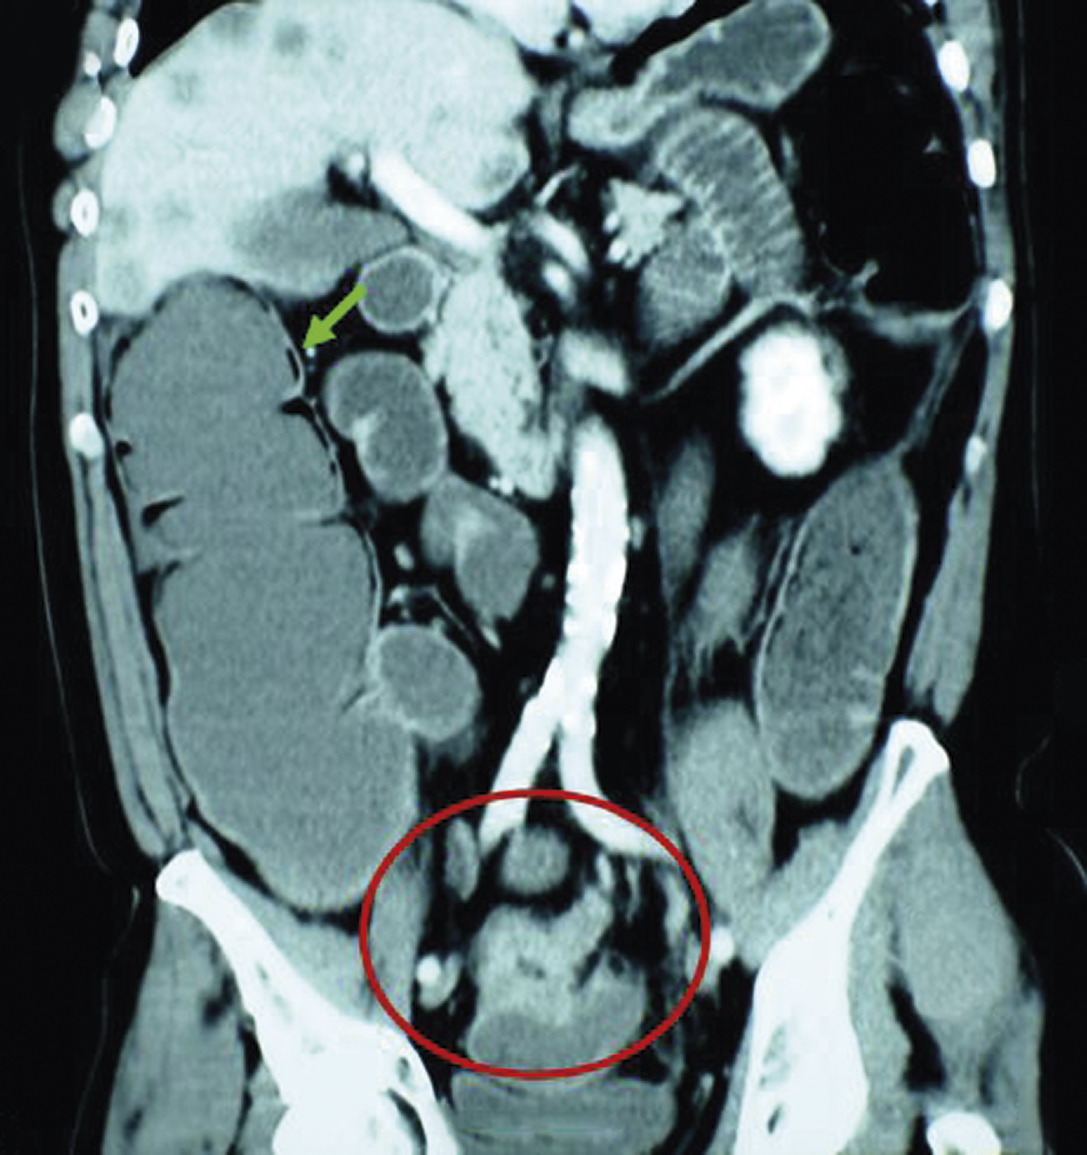

Les signes tomodensitométriques décelés sur le site de torsion sont classiquement (fig. 1 et 2) :

• anses dilatées, en forme de « U » ou de « C », à distribution radiaire ;

• présence de deux anses adjacentes collabées de forme ronde, ovale, triangulaire au niveau du site d’obstruction ;

• whirl sign, ou signe du tourbillon, qui correspond à l'enroulement des vaisseaux mésentériques et des mésos qui convergent vers le point de torsion mésentérique (fig. 1) ;

• le signe du bec, qui correspond à la visualisation, en coupe longitudinale, d’un aspect en pointe effilée reflétant à la diminution progressive du calibre intestinal jusqu'au niveau de l’obstruction (fig. 2).